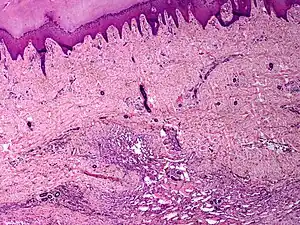

| Skin angiomatosis | |

Angiomatosis is a non-neoplastic condition[1] characterised by nests of proliferating capillaries arranged in a lobular pattern, displacing adjacent muscle and fat.[2] It consists of many angiomas.[3]

These tend to be cavernous hemangiomas, which are sharply defined, sponge-like tumors composed of large, dilated, cavernous vascular spaces.

It is a vascular malformation wherein blood vessels proliferate along with accompanying mature fat and fibrous tissue, lymphatics and sometimes nerves.[2] They may involve skin, subcutaneous tissue, skeletal muscle and occasionally bone.[2]